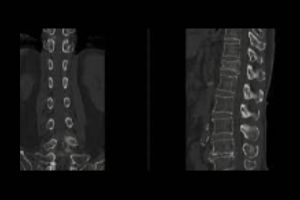

NCCT Right Leg

Are you looking for an affordable NCCT Right Leg scan? At Medifyhome, we offer competitively priced MRI and CT scans, partnering with top NABL-certified diagnostic centres and clinics. Our facilities ensure high-quality imaging and accurate results. An NCCT (non-contrast computed tomography) scan of the right leg is a diagnostic imaging procedure that provides detailed cross-sectional images of the bones and soft tissues of the leg without using contrast agents. This scan is commonly utilized to evaluate fractures, bone tumours, infections, and conditions affecting the vascular system. During the procedure, the patient lies still while the CT machine captures multiple images from different angles. The resulting high-resolution images help healthcare providers assess the integrity of the leg’s bones and surrounding tissues. The NCCT scan is quick, safe, and ideal for patients who may have allergies to contrast materials or need urgent evaluations. To book an appointment for an NCCT Right Leg scan, visit our platform, Medifyhome, or contact us at +919100907036 or +919100907622 for reasonable prices.

What is an NCCT Right Leg scan?

An NCCT (non-contrast computed tomography) scan of the right leg is a diagnostic imaging test that produces detailed cross-sectional images of the bones, soft tissues, and structures of the right leg without the use of contrast agents. This scan is used to evaluate various conditions, including fractures, bone tumours, infections, and vascular issues. It offers high-resolution images that help healthcare providers accurately diagnose and assess the extent of any problems affecting the leg. The procedure is quick and generally safe, making it suitable for patients who may be allergic to contrast materials or require immediate evaluation. Overall, the NCCT scan is a valuable tool in diagnosing and guiding treatment for leg-related issues.